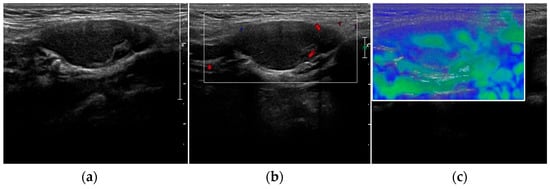

- Trimboli, P.; Dietrich, C.F.; David, E.; Mastroeni, G.; Spagnolo, O.V.; Sidhu, P.; Letizia, C.; Messineo, D.; D’Ambrosio, F.; Radzina, M.; et al. Ultrasound and ultrasound-related techniques in endocrine diseases. Minerva Endocrinol. 2018, 43, 333–340. [Google Scholar] [CrossRef] [PubMed]

- Platz Batista da Silva, N.; Jung, E.M.; Jung, F. VueBox(R) perfusion analysis of contrast-enhanced ultrasound (CEUS) examinations in patients with primary hyperparathyroidism for preoperative detection of parathyroid gland adenoma. Clin. Hemorheol. Microcirc. 2018, 70, 423–431. [Google Scholar] [CrossRef]

- Trimboli, P.; Castellana, M.; Virili, C.; Havre, R.F.; Bini, F.; Marinozzi, F.; D’Ambrosio, F.; Giorgino, F.; Giovanella, L.; Prosch, H.; et al. Performance of contrast-enhanced ultrasound (CEUS) in assessing thyroid nodules: A systematic review and meta-analysis using histological standard of reference. Radiol. Med. 2020, 125, 406–415. [Google Scholar] [CrossRef]

- Radzina, M.; Ratniece, M.; Putrins, D.S.; Saule, L.; Cantisani, V. Performance of Contrast-Enhanced Ultrasound in Thyroid Nodules: Review of Current State and Future Perspectives. Cancers 2021, 13, 5469. [Google Scholar] [CrossRef] [PubMed]